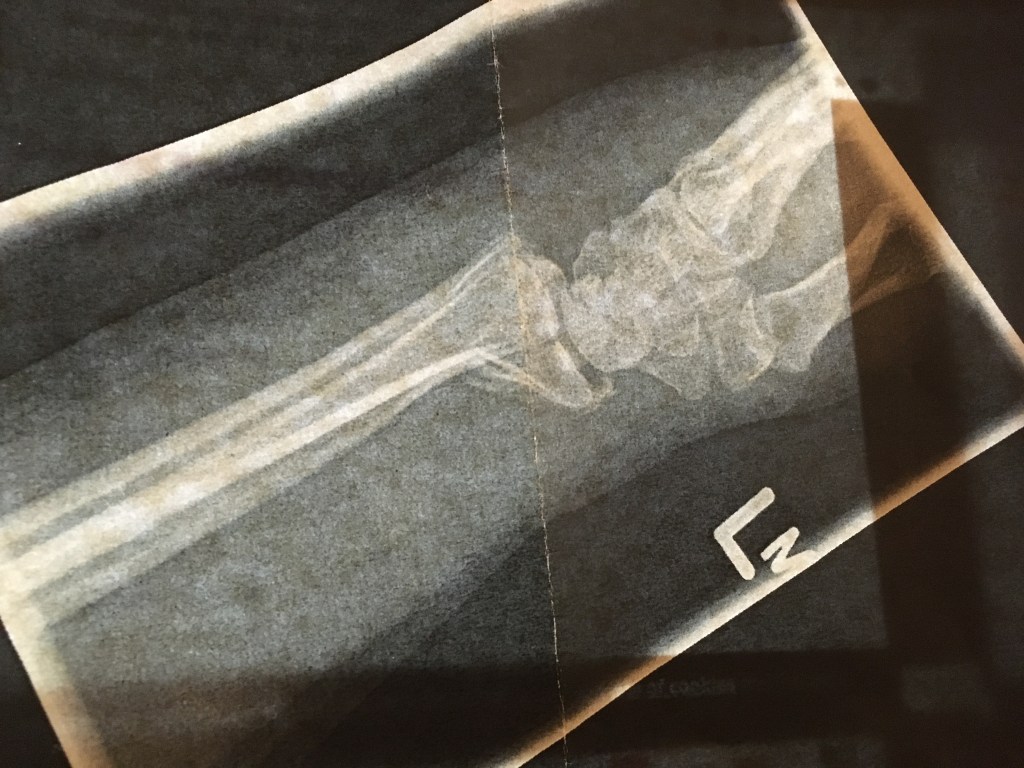

May – getting busy now and I’m testing the wrist with paddling on Lee Valley white water course. For the first time in months we do something partly indoors with others – a first aid course. Given how accident prone I am, it’s a good idea to ensure that I am able to direct people how to fix me. Mr DB will disagree since on falling off the bike and breaking my wrist I told him just to give me a minute and I’d get back on.